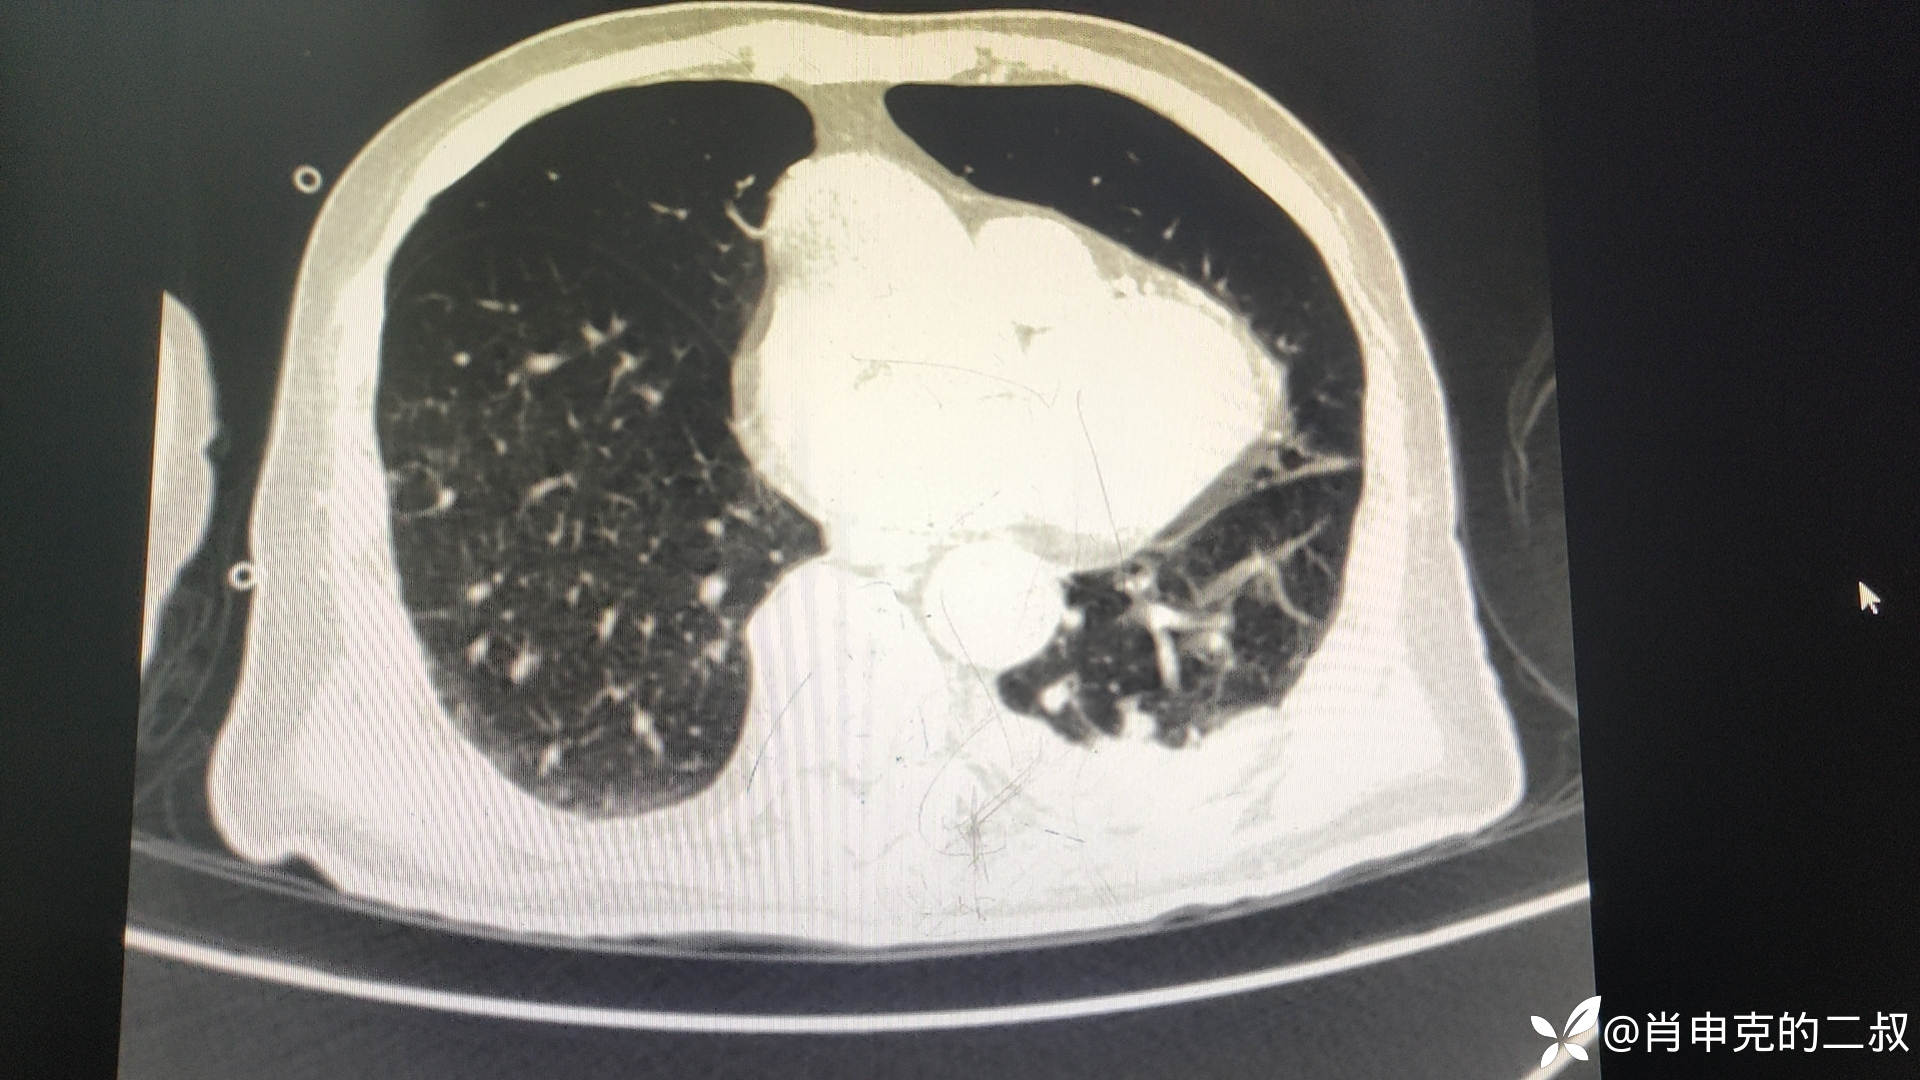

入院后急诊行腹部CT检查:可见结肠、直肠扩张明显。

见如此腹部CT,当日与患者行内镜下减压治疗。

肠梗阻管治疗第3日,复查腹部CT,并无明确好转。

此时患者,,复查CT:心包积液、胸腔积液、肺部感染、肺不张。。腹部CT反而未见特殊异常。。。